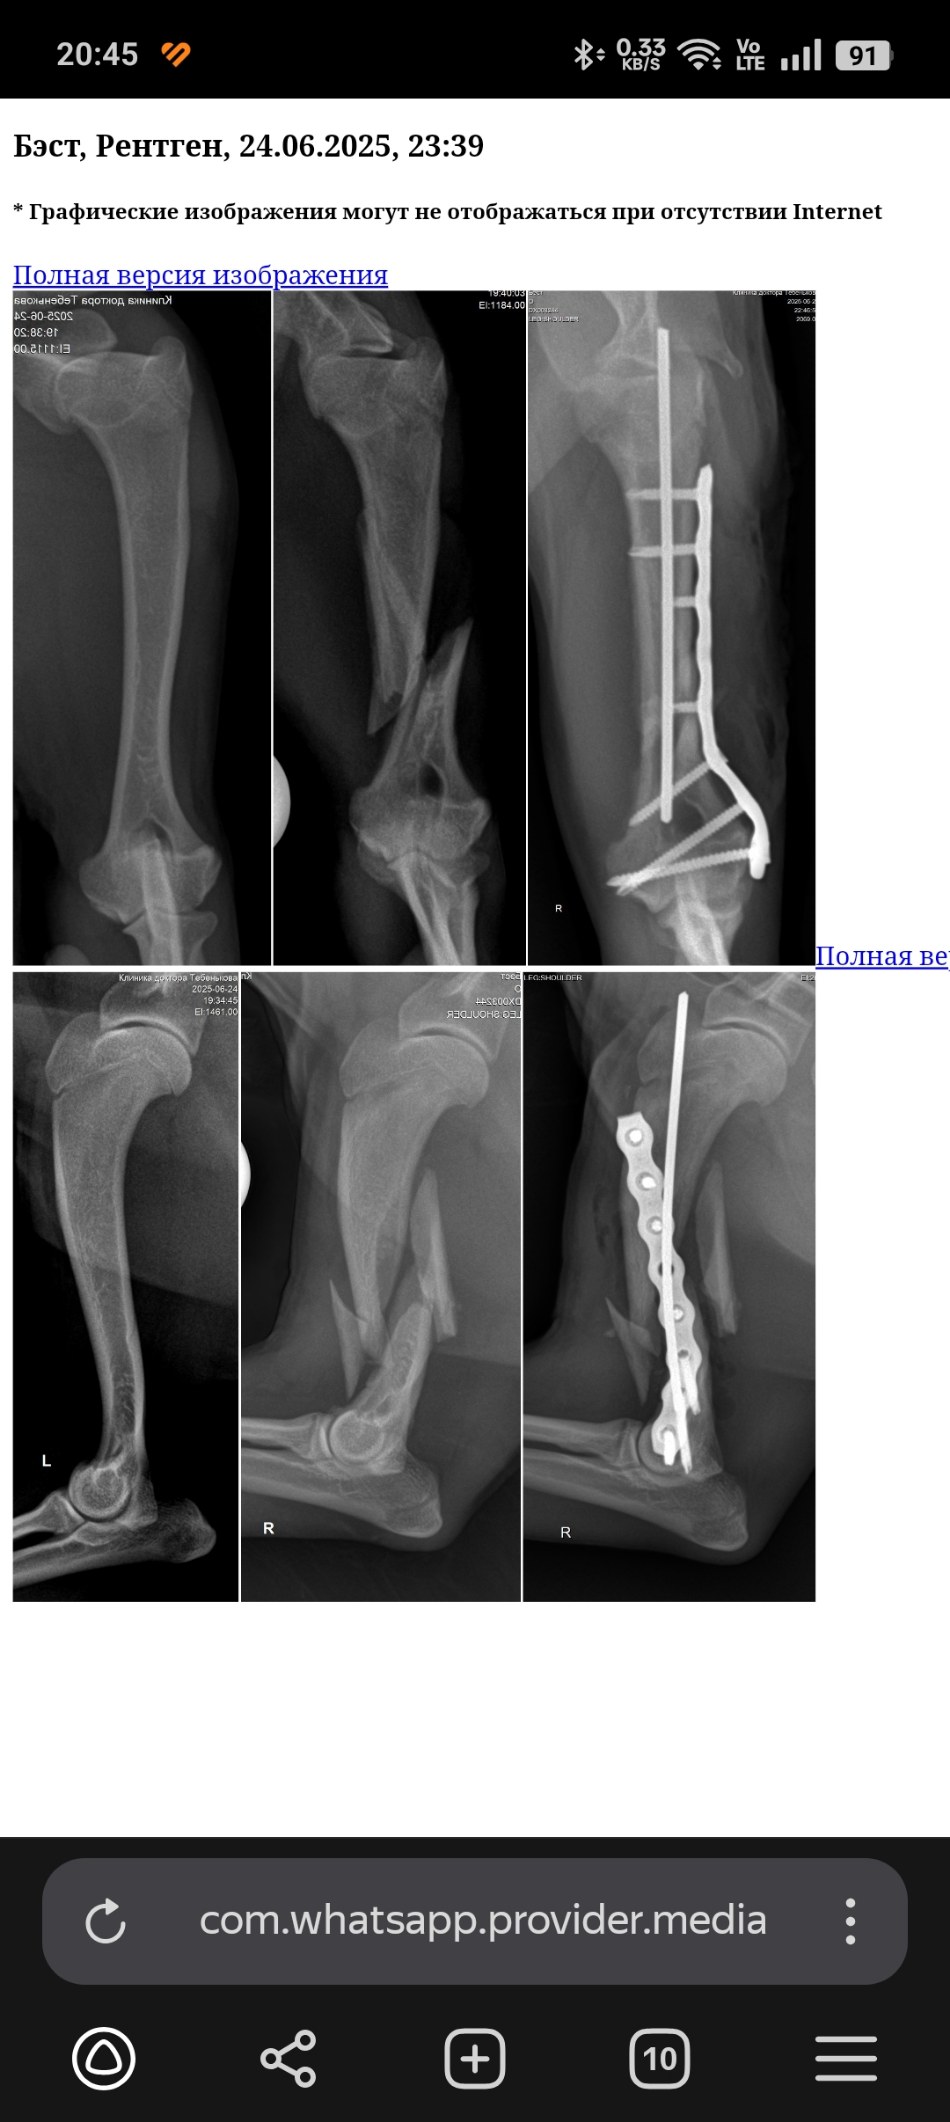

Екатеринбург, цвергшнауцер Бэст, 8 мес

Найден с переломом плеча.

Рентген до и после

Screenshot_2025-06-25-20-45-40-45_21da60175e70af211acc4f26191b7a77.jpg